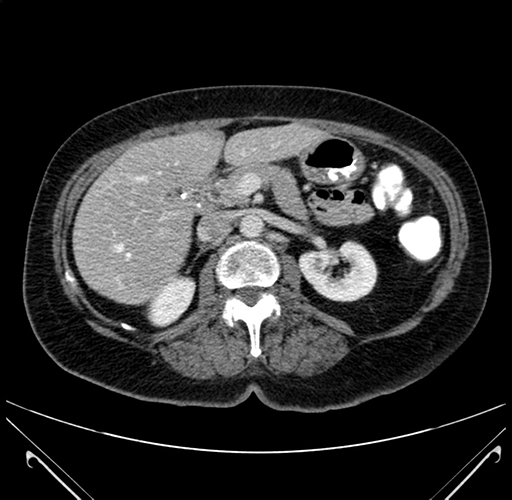

Pre-Chemo: Axial Venous

Axial Venous